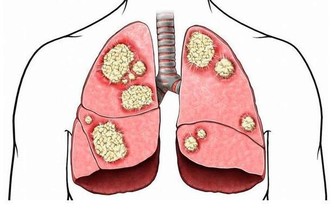

腎臟的人體內重要的排毒器官,體內的各種毒素都要需要經過腎臟的處理才能將其排出體外,一旦腎臟出現問題,則很多毒素就會積累在體內,從而也給了很多細菌以及病毒入侵的機會,所以在日常生活中,注意腎臟的健康是非常重要的,同時要適當的對腎臟進行一些益補的措施,在飲食方面也要注意,減少對腎臟的損害。